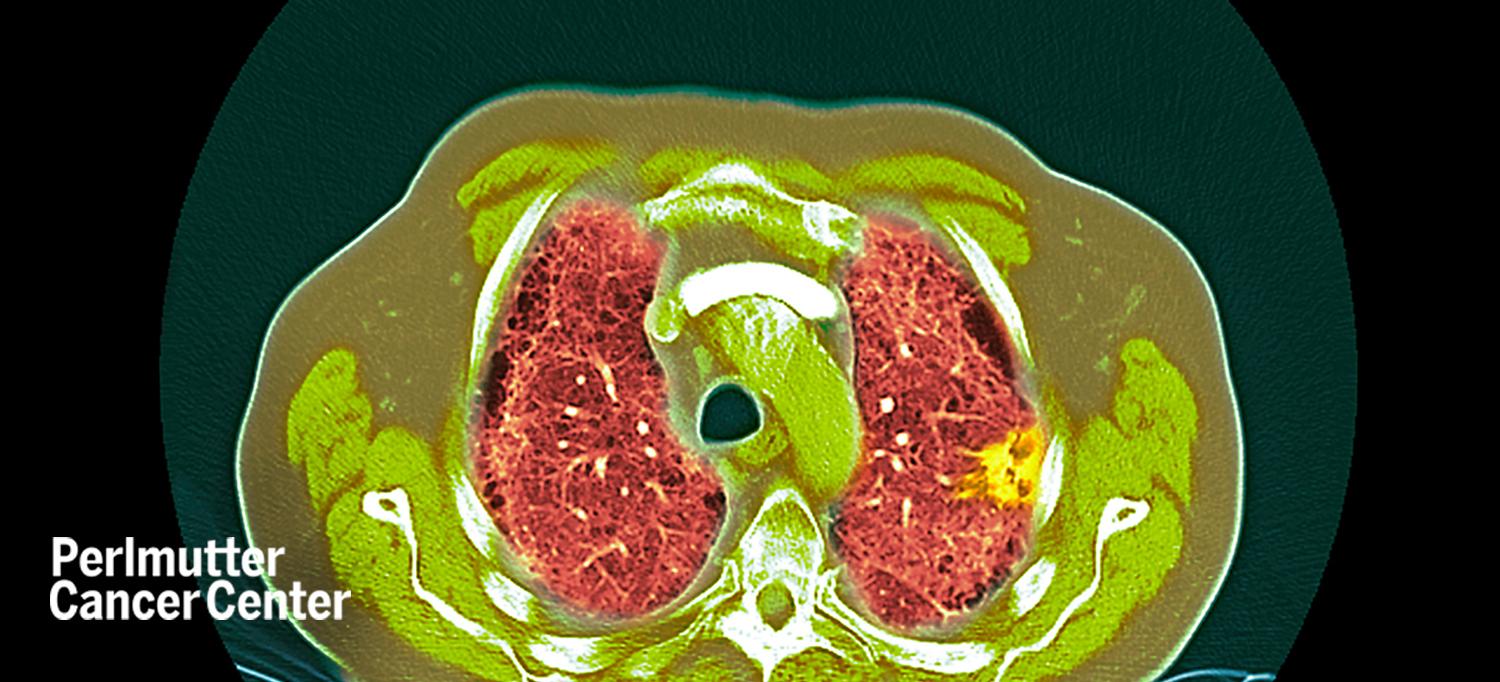

Studies have shown that using low-dose CT scans to screen for lung cancer can detect cancer early and save lives. Yet, adoption of CT scanning in the United States has been low, with only an estimated 3 to 5 percent of those eligible for screening actually receiving scans.

Abraham Chachoua, MD, the Jay and Isabel Fine Professor of Oncology in the Department of Medicine and associate director of cancer services at NYU Langone Health’s Perlmutter Cancer Center, talks with OncLive On Air about the cancer center’s new Lung Cancer Screening Program, how it is implemented using electronic medical records to identify eligible people, and the financial implications of screening.